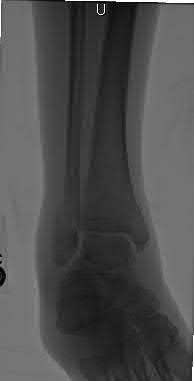

Figures A to C show radiographs of a 70 year-old male who fell on the ice 5 days ago. He could initially walk after the fall, but he is now unable to weight-bear on the leg due to pain. Physical examination shows diffuse ankle swelling, with no medial sided ankle tenderness. He is neurovascularly intact. The patient does not smoke and has no medical history. A gravity stress radiograph is demonstrated in Figure

D. After closed reduction, there is 2 mm of fracture displacement, no talar shift and the talocrural angle = 83 degrees. What is the most appropriate treatment?

Figure D demonstrates a stress radiograph with minimal medial clear space widening.